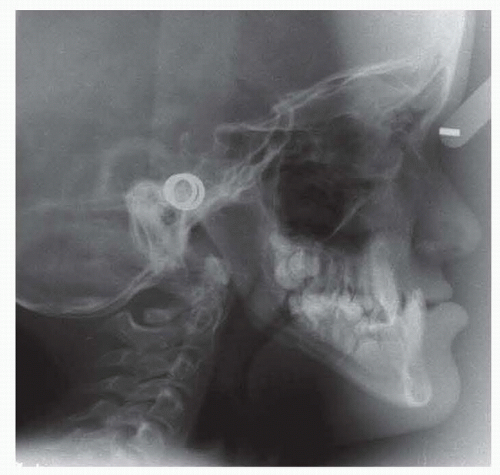

Cephalograms and photographs are used for preoperative planning and postoperative comparisons (FIG 2).